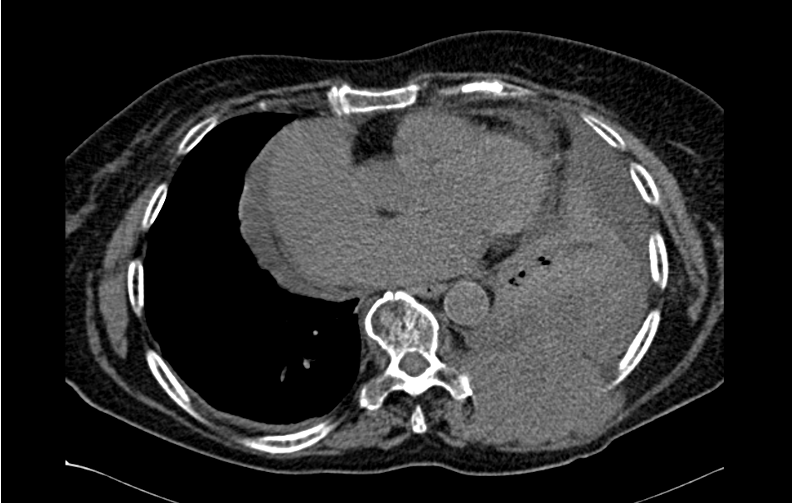

Xanthogranulomatous Pyelonephritis: An Uncommon Form of Pyelonephritis Highlighted in a Case Report

Danielle Malavazi Oliveira; Bárbara Sthefany de Paula Lacerda; Matheus Compart Hemerly, Maria Isabel Lima dos Santos, Weverton Machado Luchi